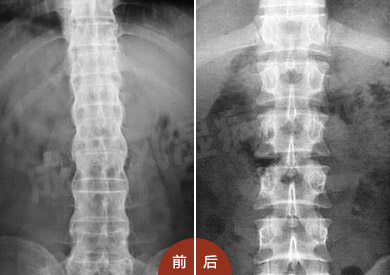

来自安阳市北关区的邵先生来到我院(郑州痛风风湿病医院)后,在2015年时,出现强直性脊柱炎早期症状。经多家医院检查未果后,邵先生只能服用止痛药来缓解病痛,随后病情加重。2014年3月,在市综合医院确诊...[详细]